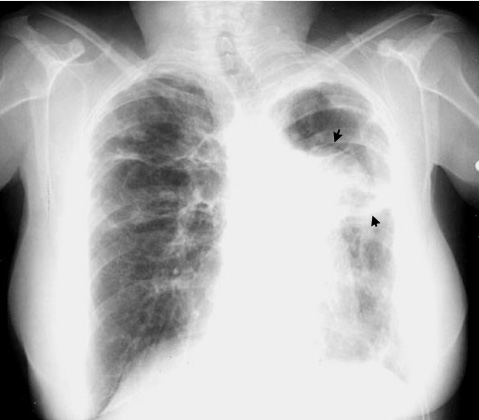

Sarcoidosis advanced stage

Advanced stage with upper lobe fibrosis; left pleural fibrosis and left upper lobe cavity with fungus ball.